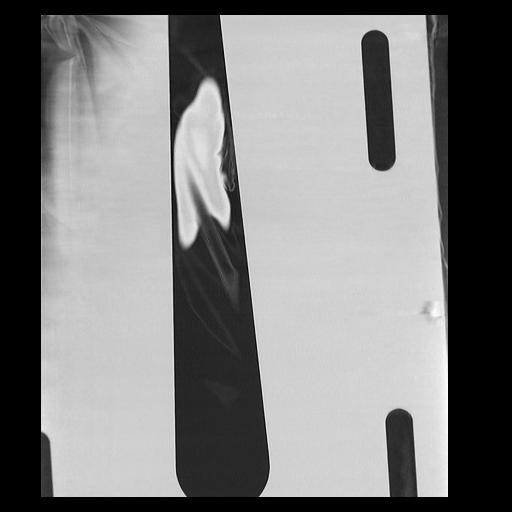

32 PULMON,CE,Coronal,3.000,PULMON,Coronal,